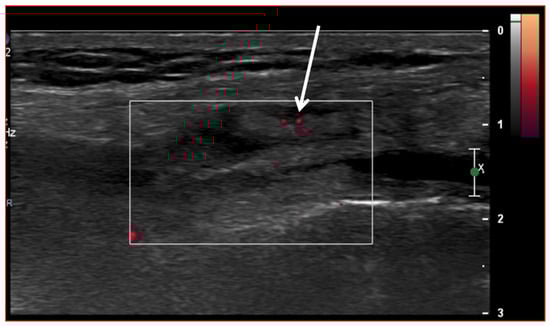

Furthermore, a US is often the first choice for image-guided minimally invasive treatments (e.g., drug injections) in the knee joint due to the wide diffusion and availability of this imaging modality, its low costs, the absence of ionizing radiation, and the possibility of real-time assessment of the needle position (Figure 8).

Figure 8.

Ultrasound-guided intra-articular lateral needle (20 Gauge—arrow) approach into a suprapatellar recess distention (blue line) with abundant joint fluid collection (asterisk) in a patient with knee osteoarthritis. Fluid aspiration and corticosteroid injection have been performed under ultrasound guidance.